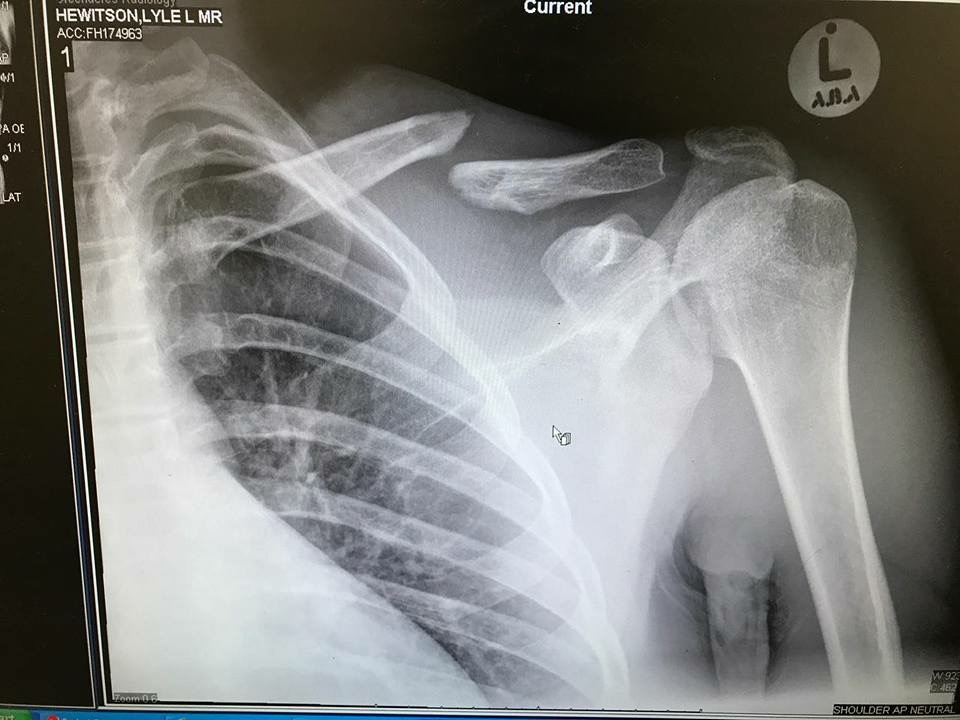

Get well soon Lyle Hewitson

Thats what you call a proper job..... get well soon young man.... PS, I hope one of the docs picked up the mouse sitting just outside his rib cage

Collar Bone